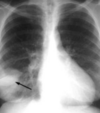

19

Q

A

Patrón intersticial reticular

How well did you know this?

1

Not at all

2

3

4

5

Perfectly